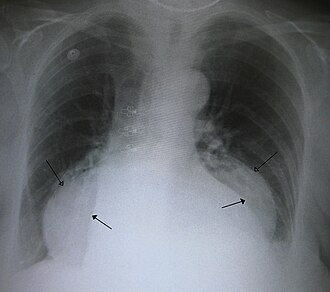

Hijatalna kila (lat. hernia hiatalis je protruzija ili hernijacija gornjeg dijela želuca u prsni koš (thorax) kroz ošit (diaphragma). Naziva se i hijatalna hernija.

Dijagnosticira se gastroskopijom ili RTG pregledom želuca u Trendelembergovom položaju koji pokaže ulazi li želudac u grudni koš.